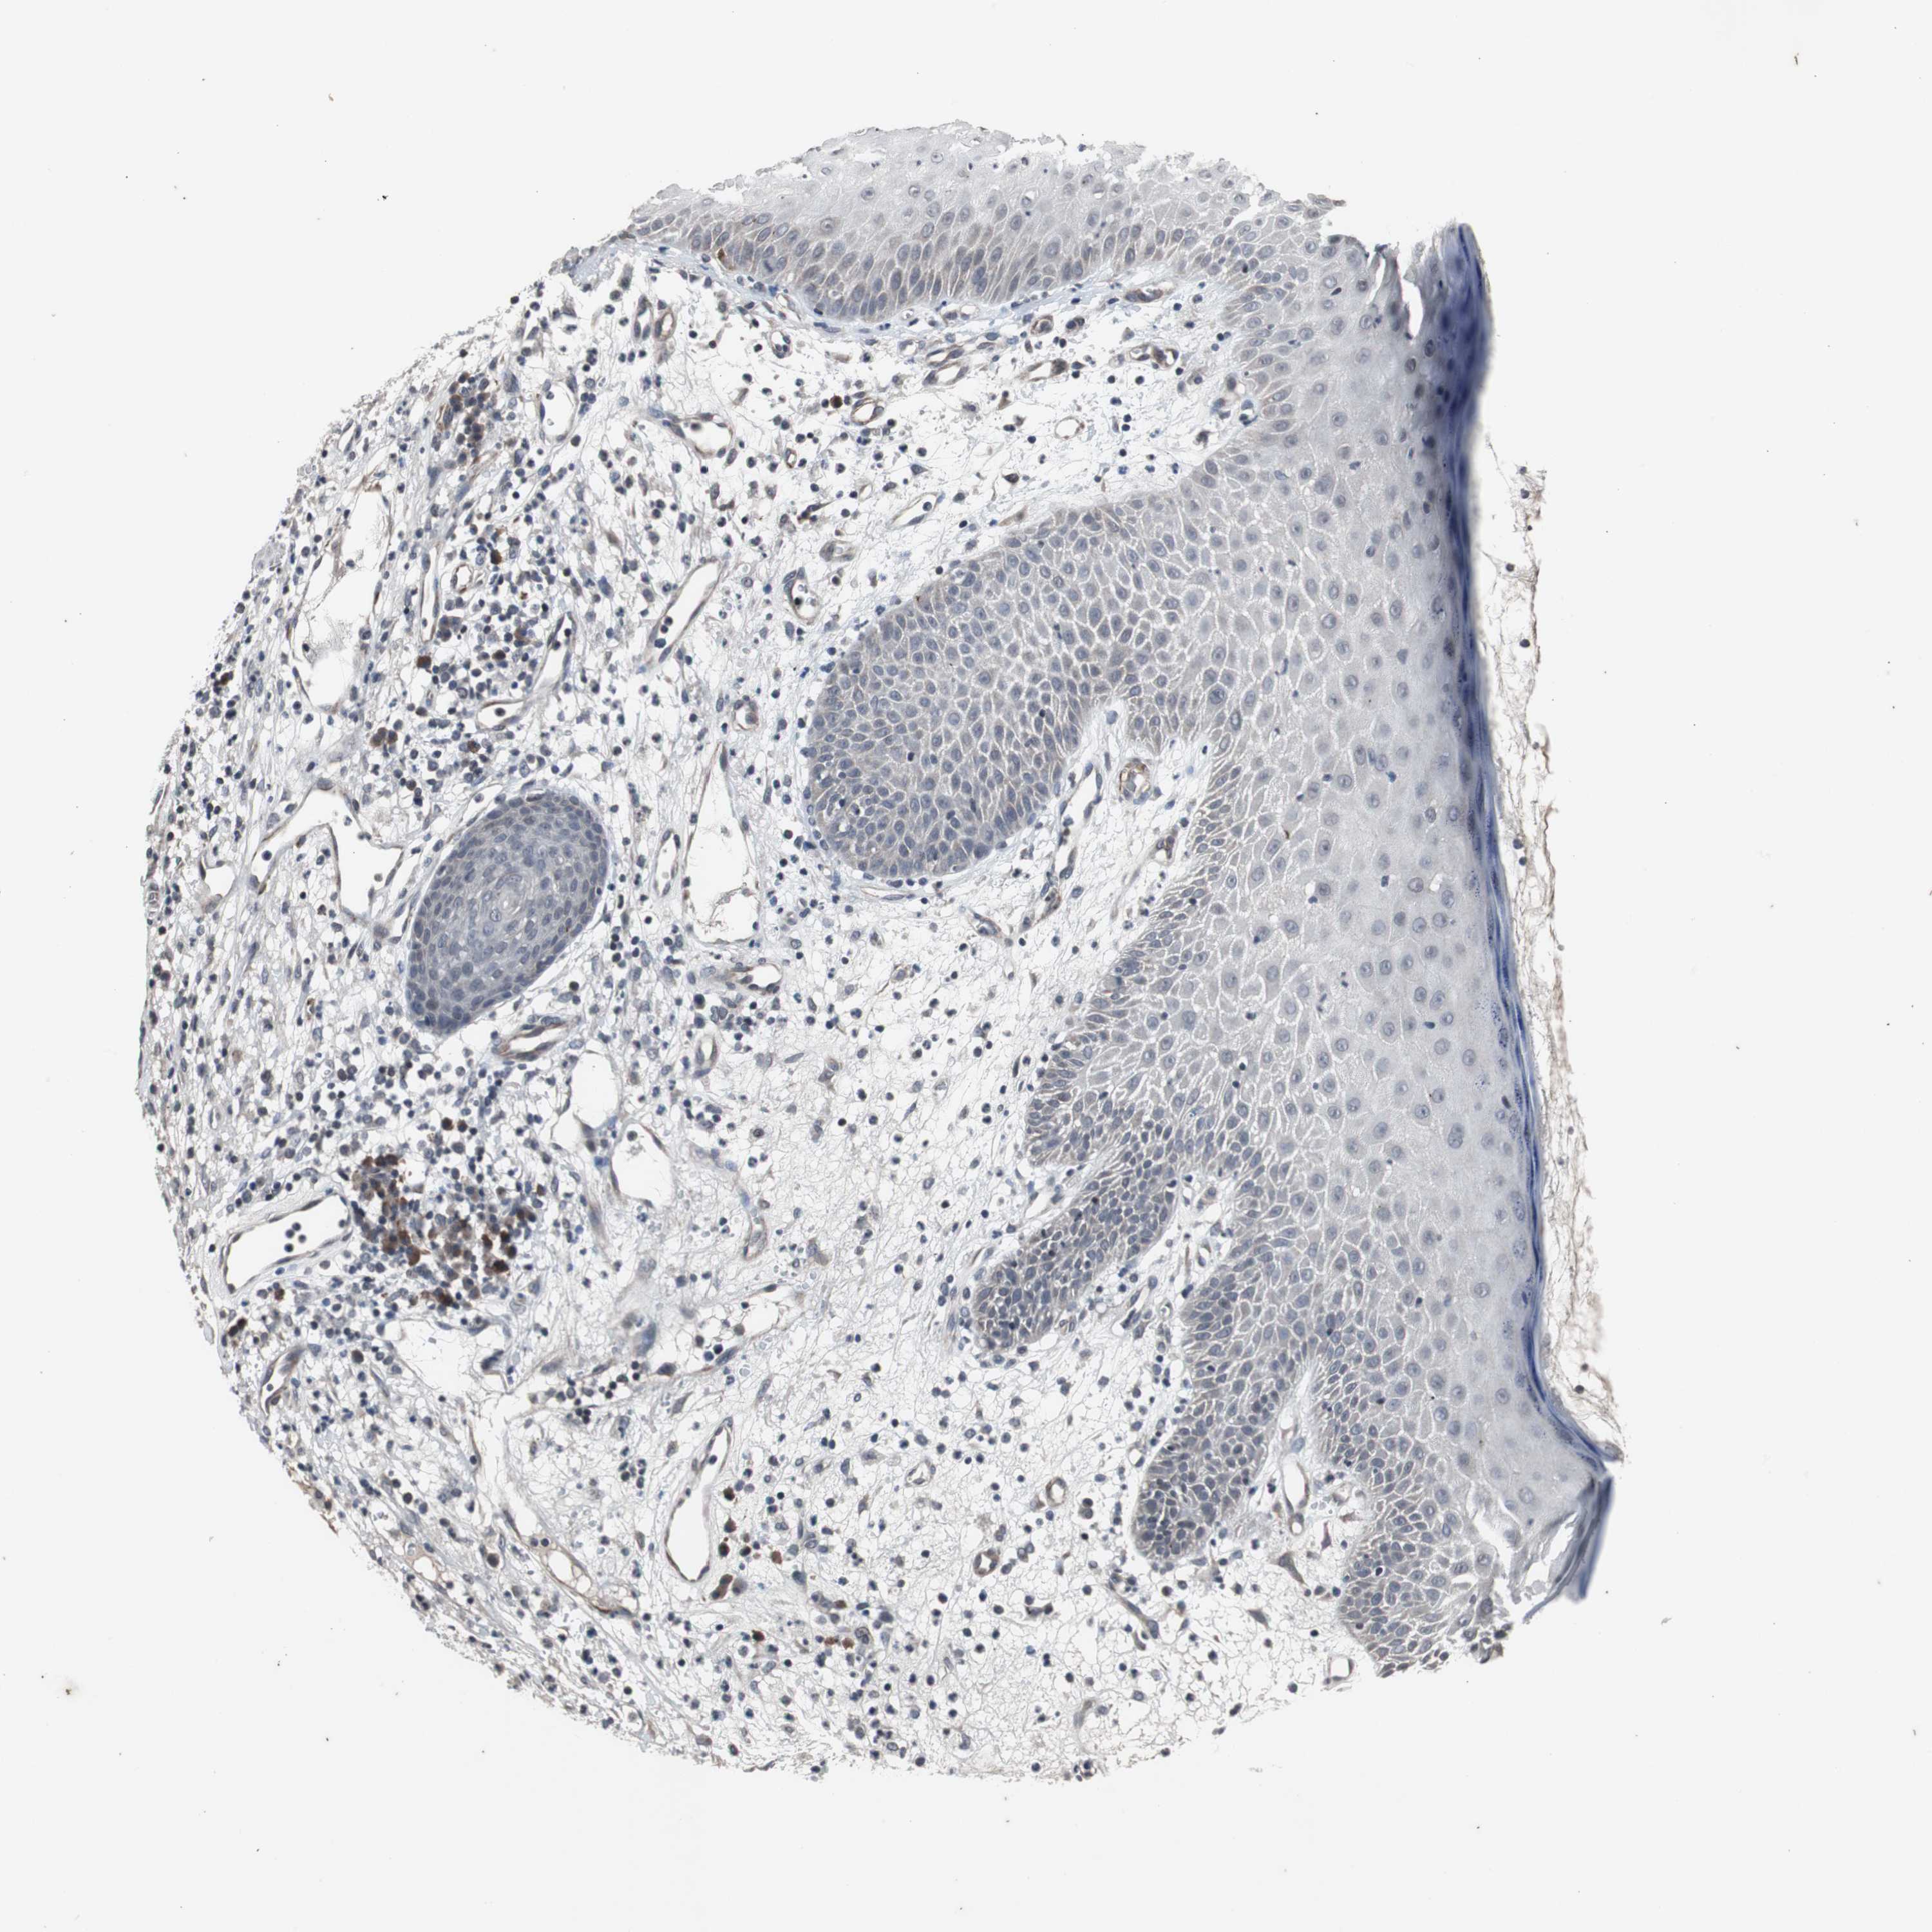

SKIN CANCER - Protein expressioni

A mouse-over function shows sample information and annotation data. Click on an image to view it in a full screen mode. Samples can be filtered based on level of antibody staining by selecting one or several of the following categories: high, medium, low and not detected. The assay and annotation is described here.

Each image is clickable and will lead to virtual microscopy that enables deeper exploration of all samples and also displays staining intensity scores, fraction scores and subcellular localization as well as patient and tissue information for each sample.

Antibody CAB005337

Staining

High

Medium

Low

Not detected

Intensity

Strong

Moderate

Weak

Negative

Quantity

>75%

75%-25%

<25%

None

Location

Nuclear

Cytoplasmic/membranous

Cytoplasmic/membranous,nuclear

Squamous cell carcinoma, NOS

Squamous cell carcinoma, metastatic, NOS

Basal cell carcinoma

Papilloma, NOS